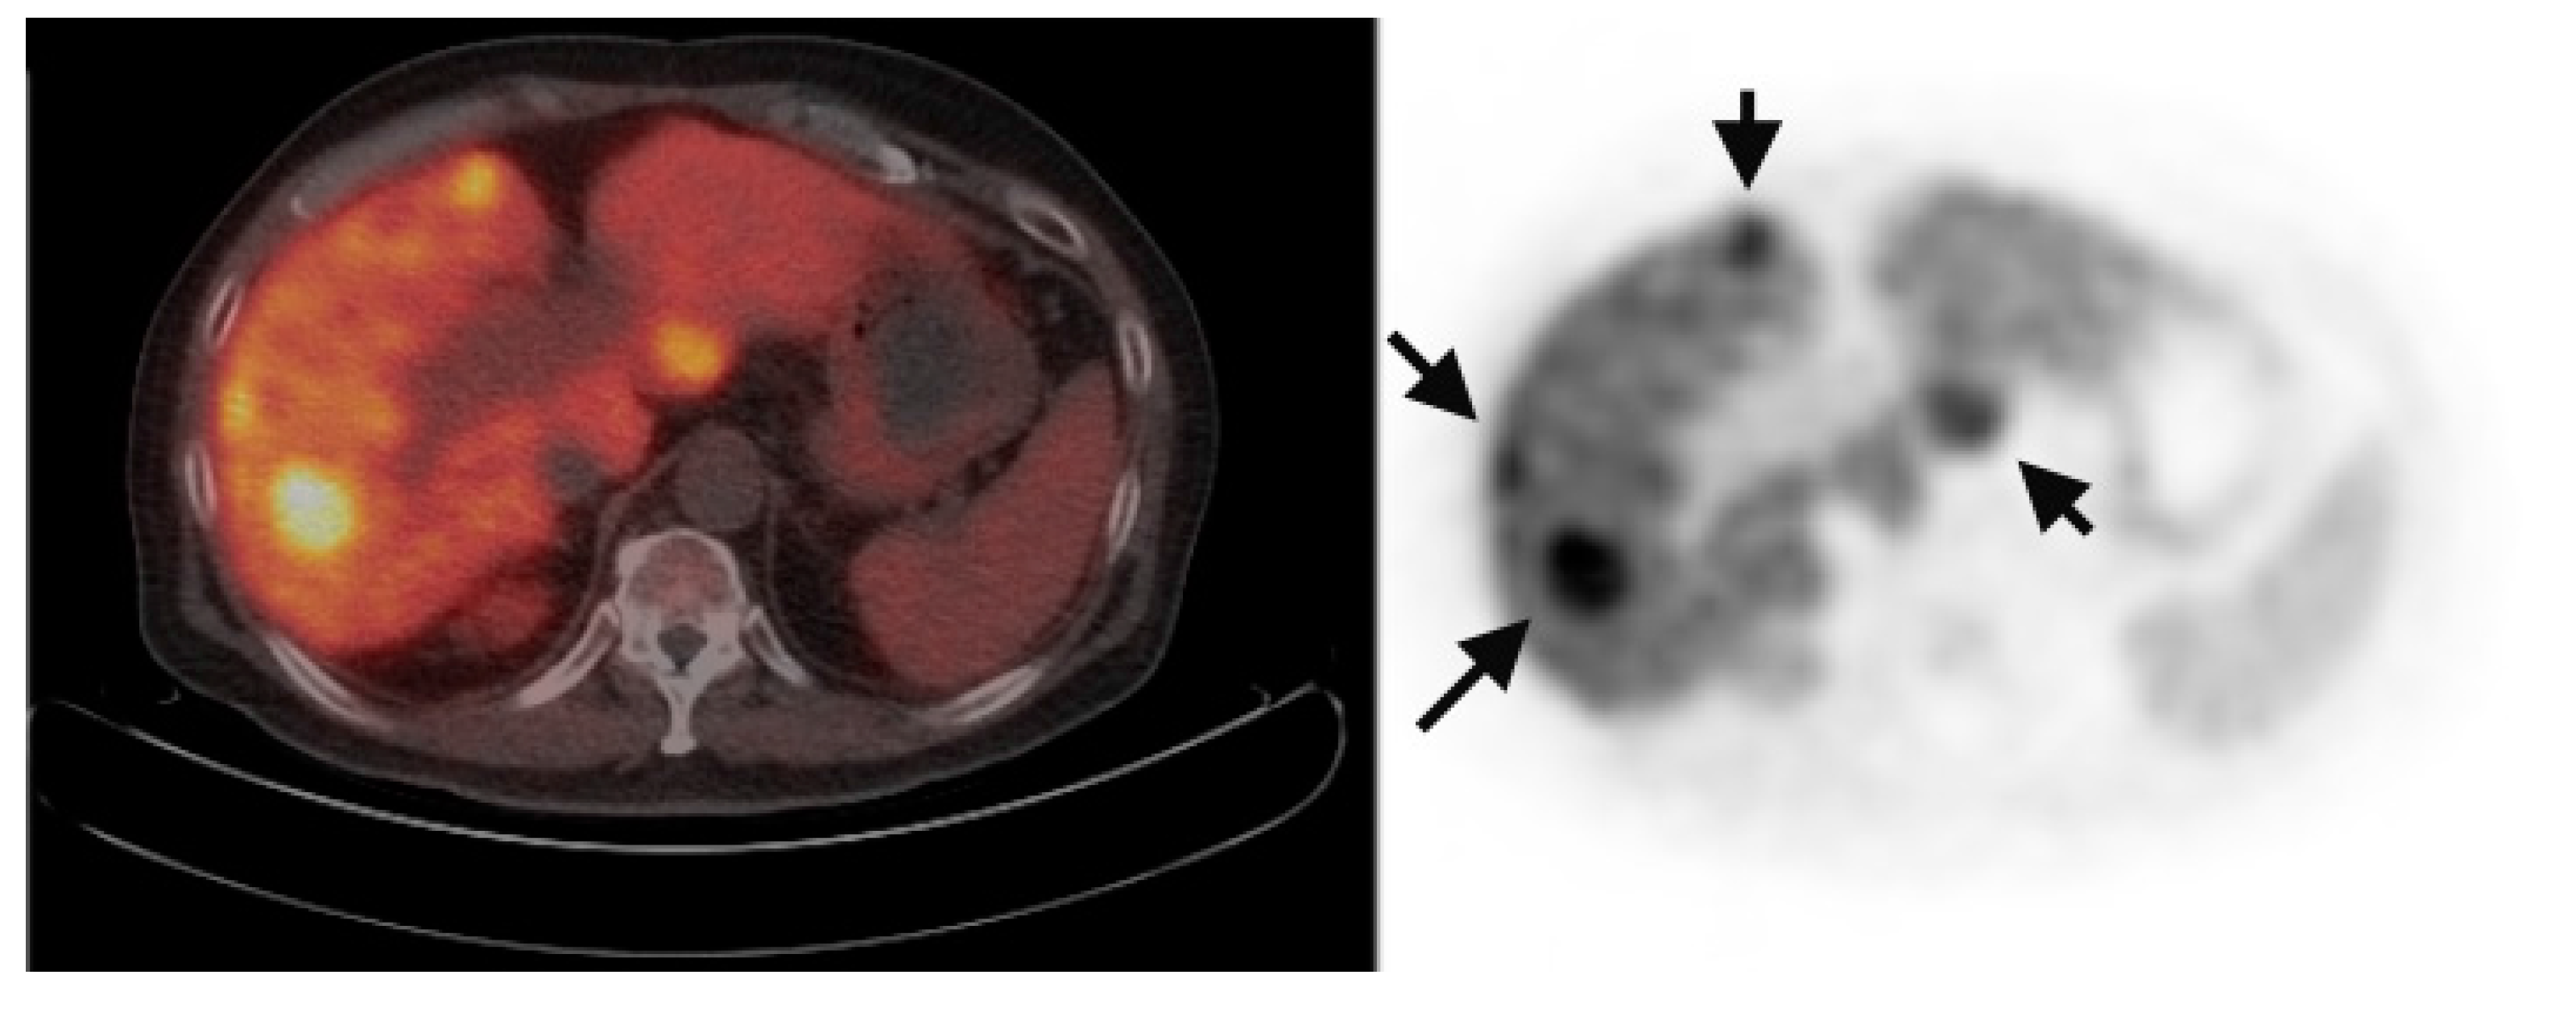

Multiple foci of increased FCh uptake in the liver consistent with multifocal or multinodular HCC (example, Figure 1) were noted in 8 of the 13 patients with increased primary tumor uptake. Of these, the areas of increased FCh uptake were adjacent to the treatment site (examples, Figure 2 and Figure 3) in 2 patients treated by local tumor ablation and 1 patient treated by liver resection. In one newly diagnosed case, PET demonstrated heterogeneous tumor FCh uptake with increased peripheral uptake and markedly diminished central uptake (Figure 4). Pathology in this case revealed a highly-necrotic tumor with Edmondson-Steiner grade 3 differentiation.

Figure 1.

Multifocal recurrent hepatocellular carcinoma (HCC). Corresponding positron emission tomography (PET)/computed tomography (CT) (left) and PET (right) images demonstrate multiple foci of increased fluorocholine (FCh) uptake in the liver (arrows) ranging in diameter from 7 to 30 mm.